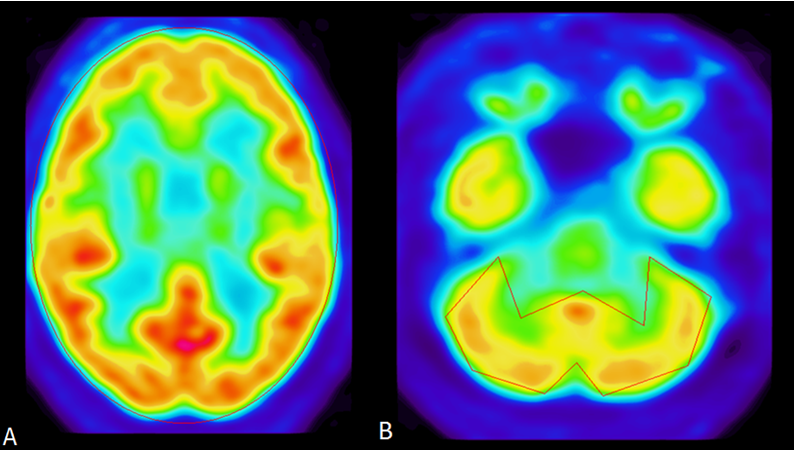

PET scan analysis exhibited a decrease in the neocortical to cerebellar ratio (mean of neocortex/mean of cerebellum) with a value of 0.82 whereas the controls averaged 1.04, standard deviation=0.08, z-score= -2.77, p-score = .0056 (Figure 1a,b). Decreased neocortical to cerebellar ratio is seen in individuals at high risk for CTE such as ex-NFL football players.38,39 This decrease in neocortical to cerebellar ratio is consistent with diffuse neocortical damage resulting in widespread reduction in metabolism relative to the cerebellar baseline. Decrease in metabolism in the frontal cortex relative to occipital cortex was also noted. The frontal to occipital lobe ratio is 0.80 in the defendant whereas the controls averaged 0.94, standard deviation=0.06, z-score= -2.24, p-score = 2.5E-02 (Figure 2). This decrease in frontal cortex relative to occipital cortex ratio means that the diffuse damage is greater in the frontal region compared to an occipital baseline.

Figure 1 PET images of Neocortical to Cerebellum Region of Interest (ROI) analysis. Defendant has decreased neocortex to cerebellar ratio compared to normal controls consistent with someone who has sustained multiple traumatic brain injuries causing diffuse decrease in neocortex relative to the cerebellum. Seen in patients at high risk for CTE such as ex-NFL football players. A, The mean neocortex for ROIs is 1.00 whereas controls averaged 0.97, standard deviation=0.01, z-score= 2.21, p-score = 2.7E-02. B, The mean cerebellum for ROIs is 1.11 whereas controls averaged 0.94, standard deviation=0.07, z-score= 2.35, p-score = 1.9E-02.

Figure 2 PET images of Frontal to Occipital Lobe Region of Interest (ROI) analysis. The mean frontal lobe/occipital lobe ratio for ROIs is 0.80 whereas controls averaged 0.94, standard deviation=0.06, z-score= -2.24, p-score = 2.5E-02. A, The mean frontal lobe for ROIs is 1.01 whereas controls averaged 1.02, standard deviation=0.04, z-score= -0.28, p-score = 7.8E-02. Defendant’s frontal lobe is especially compromised. The frontal lobe is involved with impulse control and judgment. B, The mean occipital lobe for ROIs is 1.25 whereas controls averaged 1.08, standard deviation=0.05, z-score= 3.17, p-score = 1.5E-03. He showed decrease frontal lobe metabolism relative to occipital lobe when compared to normal controls.